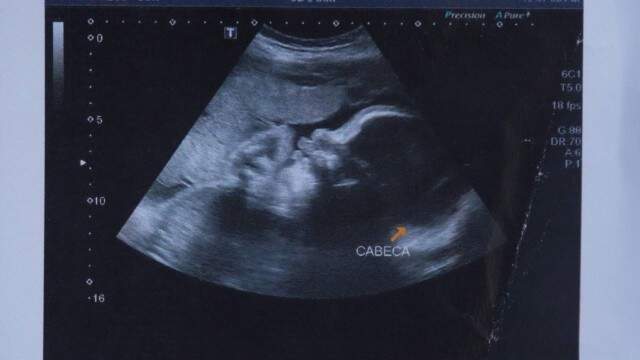

O bebê que foi baleado dentro da barriga da mãe, durante um tiroteio na Favela do Lixão, em Duque de Caxias, na Baixada Fluminense, na última sexta-feira (3), está com um coágulo na cabeça, segundo informações do secretário de Saúde de Duque de Caxias. A criança, que está internada em estado grave no Hospital estadual Adão Pereira Nunes, na Baixada Fluminense, também está paraplégica, de acordo com boletim médico.

O bebê estava no nono mês de gestação quando foi baleado na orelha e no ombro. O tiro entrou na coxa esquerda de sua mãe. Na ocasião, a mulher havia acabado de sair de um mercado quando começou um confronto entre traficantes da Favela do Lixão, onde mora, e policiais militares do 15º BPM (Caxias). Os PMs afirmaram , em depoimento na 59ª DP (Caxias), que foram atacados e não reagiram.